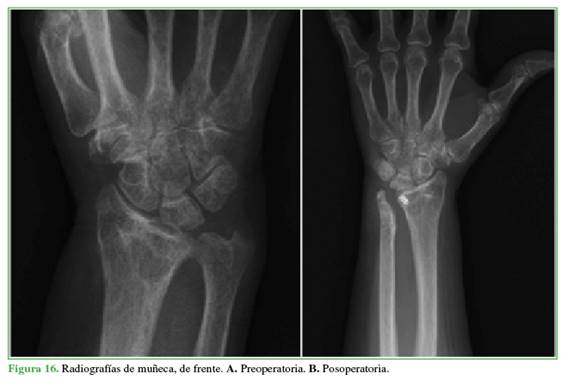

En la Figura 16, se muestran las radiografías pre y posoperatorias de un paciente y, en la Figura 17, imágenes pre y posoperatorias de otro caso de la serie.